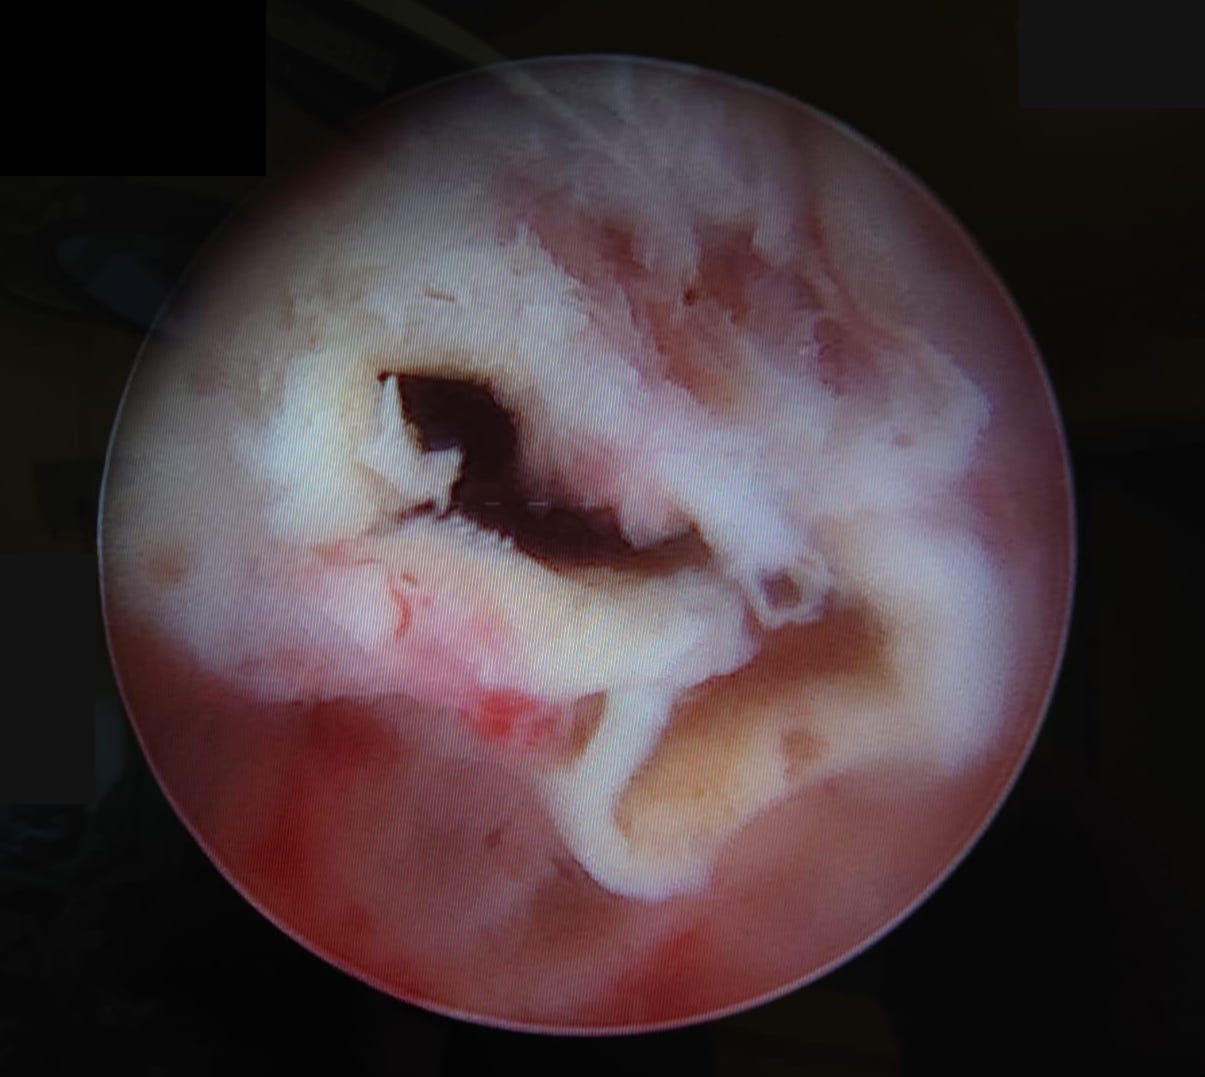

Pathologies of the pineal gland region are frequently encountered in daily neurosurgical practice. It is important to remember that, besides usually asymptomatic pineal gland cysts, neoplasms of a different origin may also occur in this region. The rarity of the most dangerous lesions – pineal gland apoplexy and pineal tumors – might cause problems with proper diagnosis and treatment. Their occurrence is commonly associated with symptomatic hydrocephalus caused by aqueductal stenosis. Currently, in such cases, endoscopic procedures, including endoscopic third ventriculostomy (ETV), are commonly and widely chosen as treatment options. Endoscopic procedures not only enable decompression of hydrocephalus but also further diagnosis of its cause. Herein, we present 3 case reports of endoscopic treatment with ETV performed in patients with hydrocephalus related to pineal region pathologies.